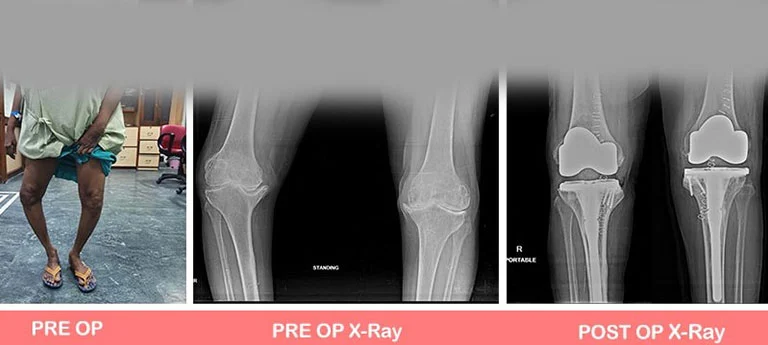

People may have certain deformities of the knee which include bow legs (varus), knock knees (valgus), or even wind-swept legs.

In such cases, the surgeon has to be well-experienced in handling such cases and should also have had considerable experience with revision joint replacement surgeries as well. See below Images.

1. Bow Legs (Varus Knee)

Some Common Deformities

1. Bow legs (Varus)

You can see illustration and X-Ray images shown above already.